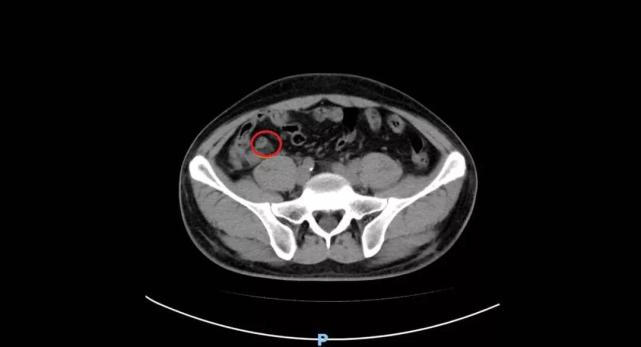

小心误诊这可不是急性阑尾炎

图片尺寸677x575